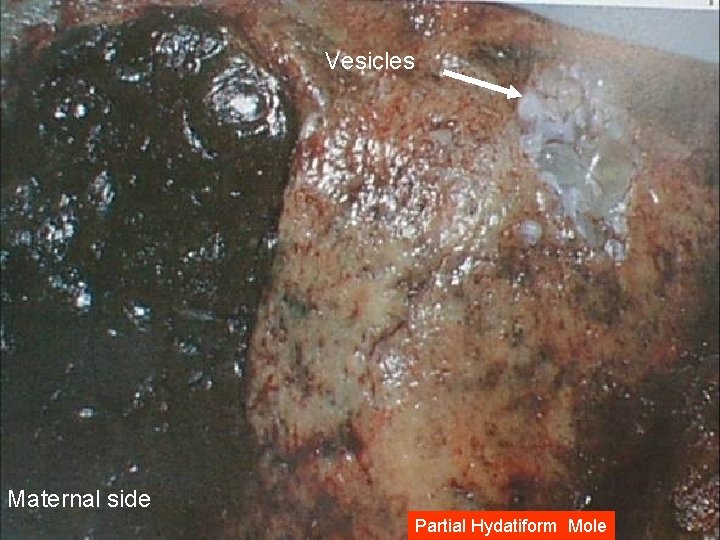

Partial H. Mole Microscopically: The enlarged, edematous villi and abnormal trophoblastic proliferation are slight and focal and did not involve the entire villi. There is a scalloping of chorionic villi Fetal or embryonic or fetal RBCs Macroscopically: The molar pattern did not involve the entire placenta. Uterine enlargement in excess of gestational age is uncommon. Theca-lutein cysts are rare Fetal or embryonic tissue or amnion

Vesicles Maternal side Partial Hydatiform Mole